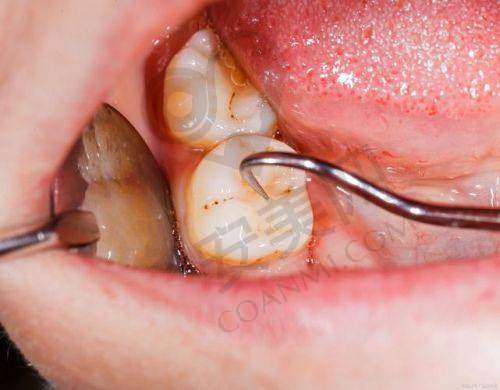

为了提高智齿拔除的正确性和安心性,玉溪舒尔口腔医院引进了一系列精良的设备。其中,口腔CT设备能够清晰地显示智齿的位置、形态以及与周围组织的关系,帮助医生制定更精细的手术方案。在拔除智齿时,使用的超声骨刀可以严谨地切割牙槽骨,减少对周围组织的损伤,降低患者的疼痛感和术后并发症的发生几率。此外,医院的消毒设备也非常精良,能够确保手术器械的严格消毒,避免交叉感染,为患者提供一个安心、卫生的治疗环境。

大部分患者在玉溪舒尔口腔医院拔除智齿后修复情况良好。由于医生在手术过程中操作精细,对周围组织的损伤较小,患者术后的疼痛感相对较轻。按照医生的护理指导,注意饮食和口腔卫生,一般在一周左右伤口就会基本愈合,肿胀和疼痛也会明显减轻。当然,不同患者的修复情况会有所差异,一些身体状况较好、智齿拔除难度较小的患者修复会更快。而对于一些修复较慢的患者,医院的医生会根据具体情况给予相应的治疗和建议,帮助他们尽快修复。